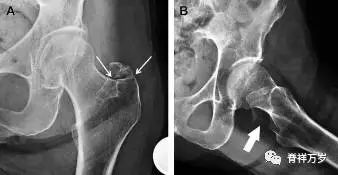

髋臼骨折最常见的类型是髋臼后壁骨折,几乎占髋关节骨折的 1/4,且常常合并髋关节后脱位。由于骨性结构重叠,可能肉眼看上去觉得非常轻微的骨折,事实却并非如此。髋臼后缘中断常常是髋臼后壁骨折的一个特征(图 1)。

图 1 为髋臼后壁骨折伴髋关节脱位患者。A 右侧髋关节 X 线片示股骨头后方可见一骨折线(箭头),髋臼后缘中断。B 左侧髋关节 X 片对照可见髋臼后缘连续(箭头)。C CT 三维重建图像示髋臼后壁缺损,可见旋转、移位的骨折块(箭头)